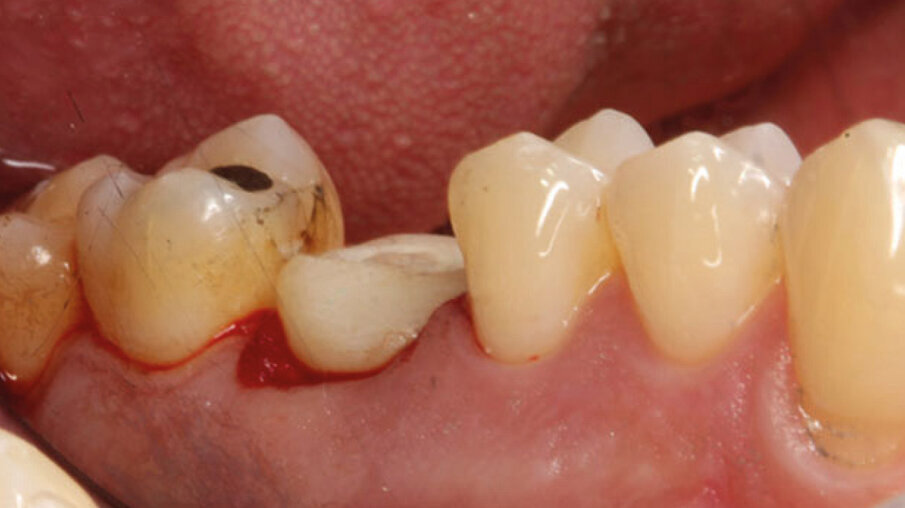

Un paziente maschio (ASA I), senza patologie croniche sistemiche e non fumatore, è stato sottoposto all’estrazione dell’elemento 16 a seguito del fallimento di terapie endodontiche e dell’impossibilità di eseguire un restauro coronale (Figg. 1a, 1b). Nella selezione del paziente sono stati criteri di esclusione: pregressa radioterapia nel distretto testa/collo, assunzione di farmaci che possano indurre ONJ, disordini ematici coagulativi, bruxismo, scarsa igiene orale domiciliare, occlusione instabile, carie non trattate, malattia parodontale non controllata, denti adiacenti a quelli da estrarre con mobilità di grado I o superiore, aspettative di risultato irreali, impossibilità o non propensi a tornare ai controlli di routine e di follow-up. La situazione dei tessuti è stata valutata pre-operatoriamente tramite radiografia periapicala (Fig. 1c) (VistaScan Mini Plus, Dürr Dental). Tramite la CBCT pre-operatoria è stato possibile fare una programmazione implantare. Sulla base dell’anatomia coronale è stata definita la posizione implantare (OnDemand3D, Cybermed), da questa analisi sono stati decisi anche il diametro e la lunghezza dell’impianto.

Fig. 1a - Foto iniziale occlusale.

Fig. 1b - Foto iniziale vestibolare.

Fig. 1c - Radiografia con cura canalare non ritrattabile, strumento rotto e probabile frattura verticale con sintomatologia da parte del paziente.